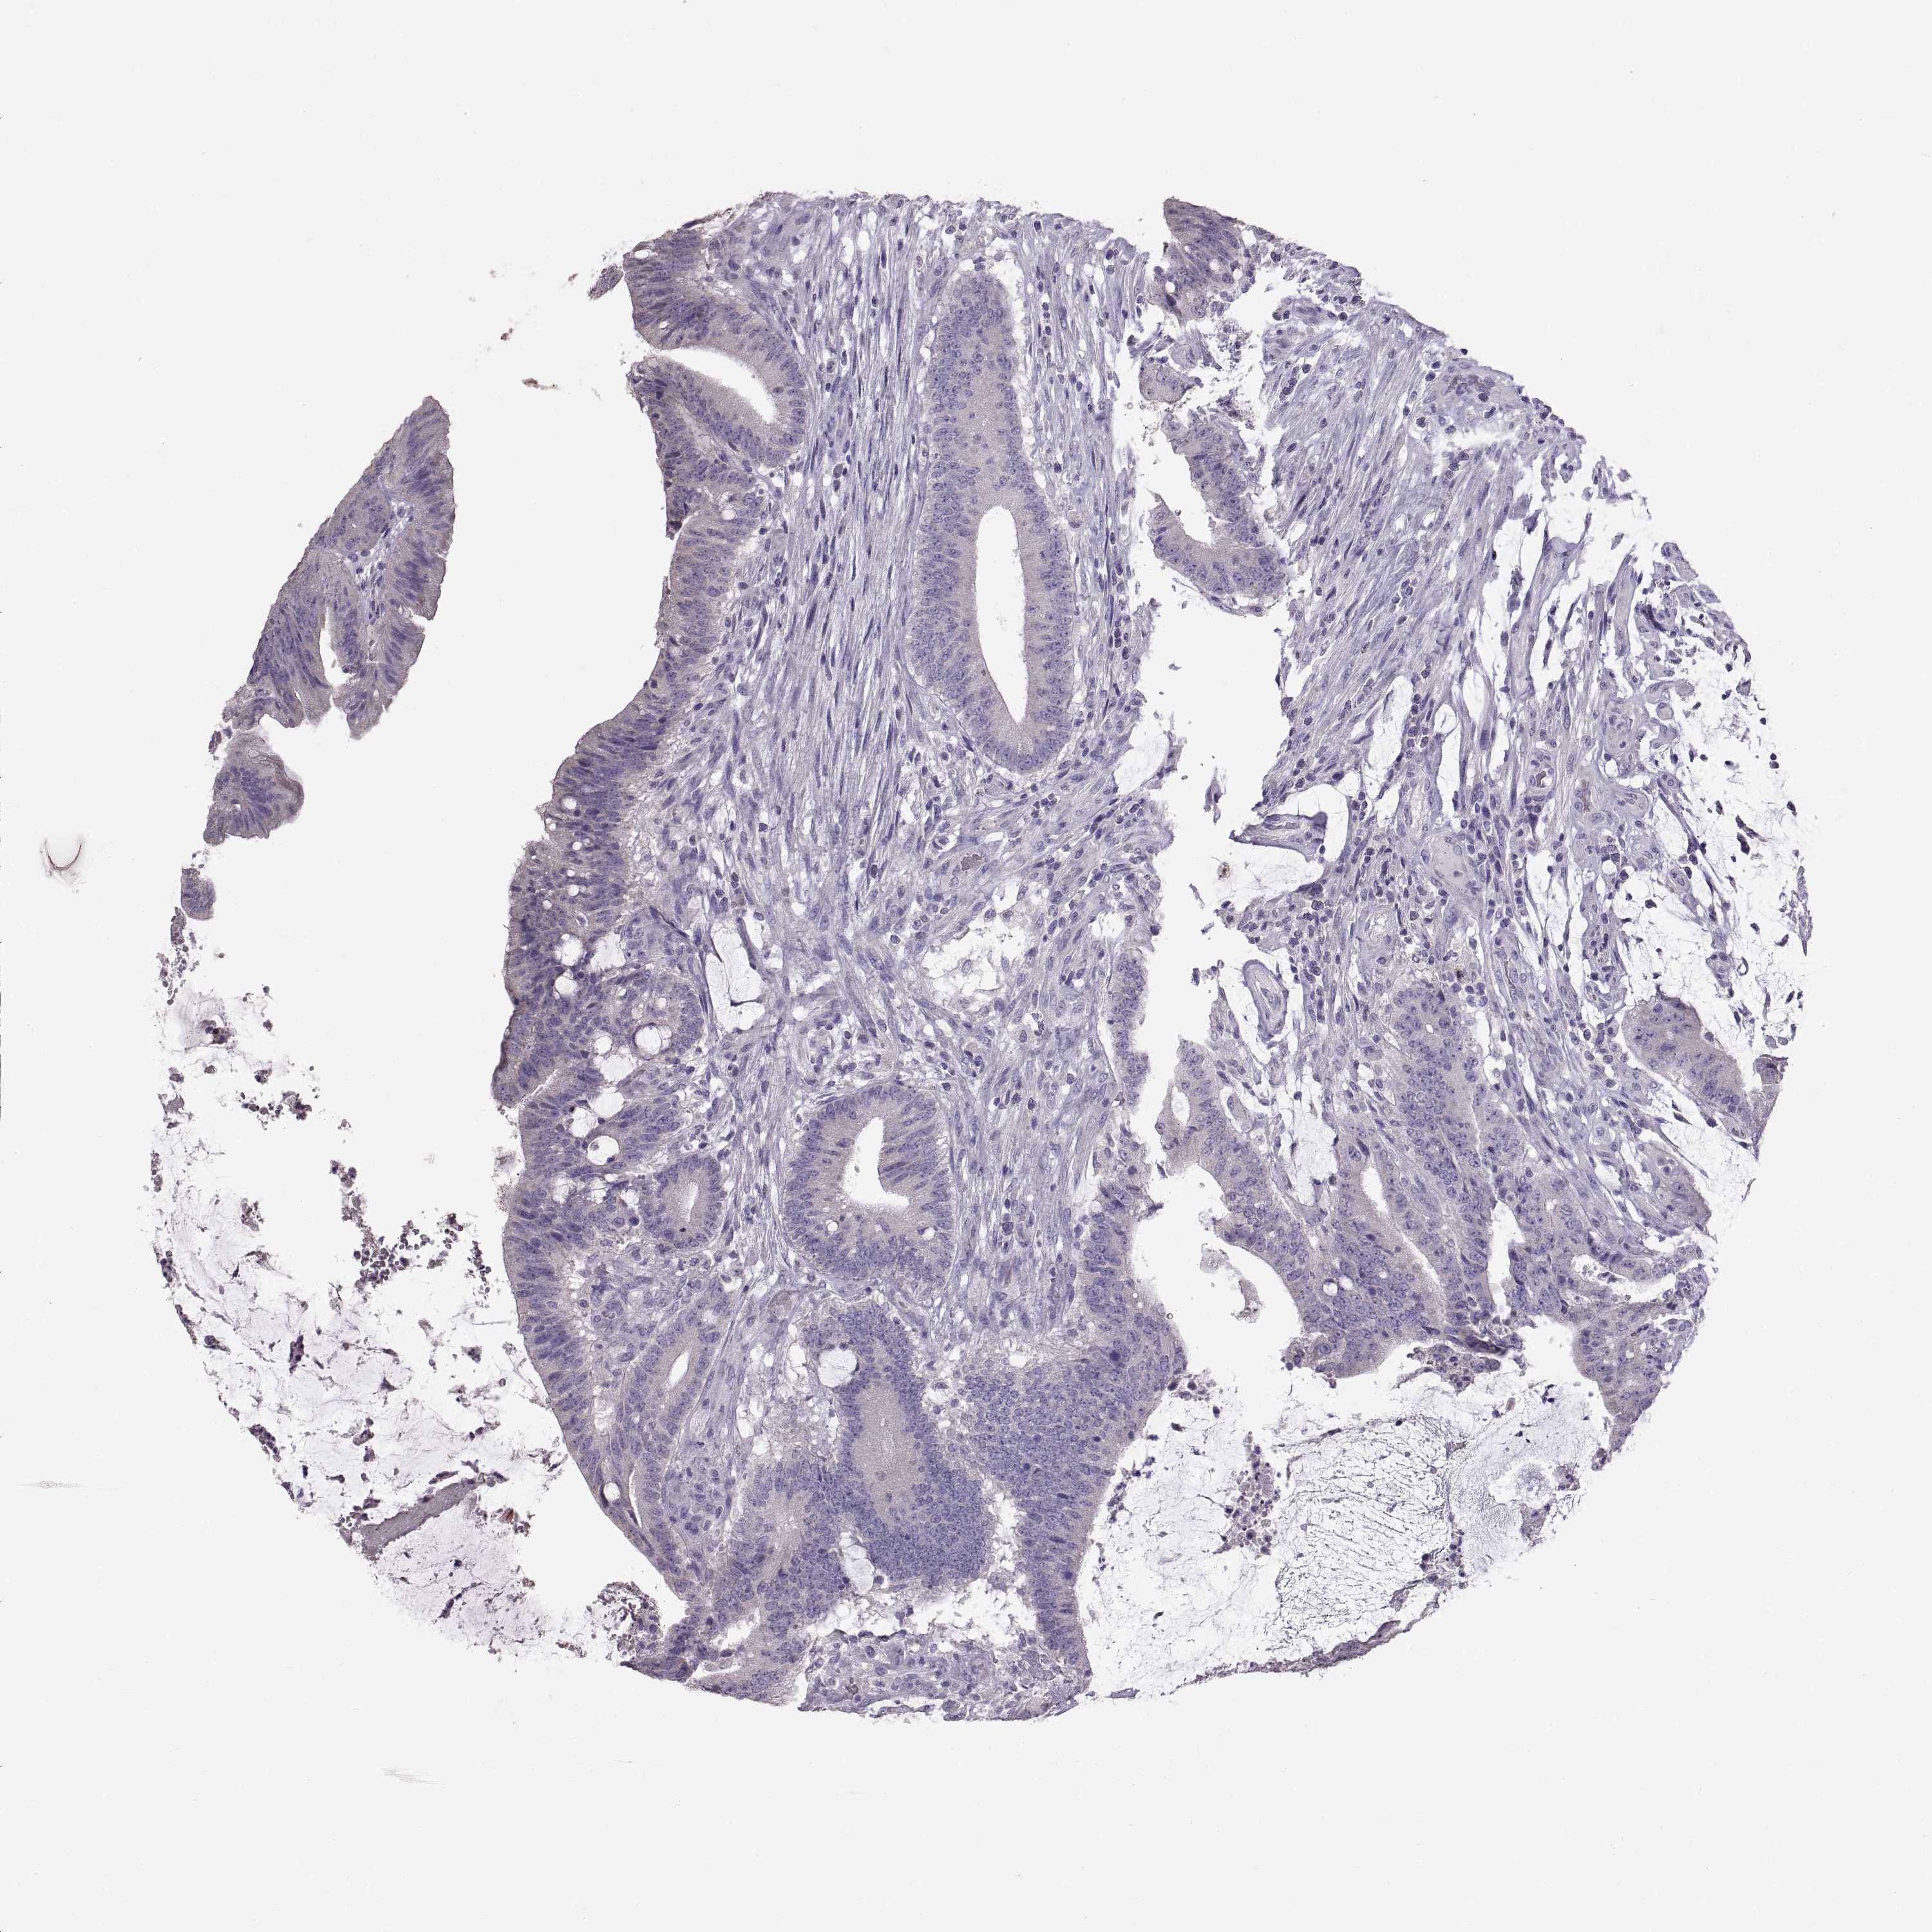

CANCER COLORECTAL CANCER Show tissue menu

Colorectal cancer

Rectum adenocarcinoma